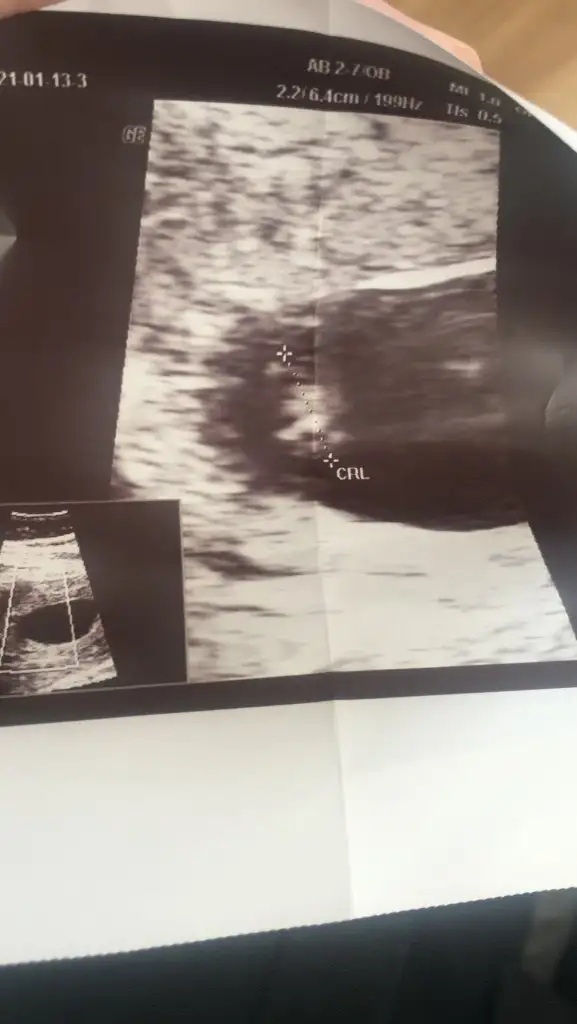

Yorumlarmisiniz rica etsem kizmi erkekmi

• 16142472949526905476915699354142.webp

16142472949526905476915699354142.webp

19,2 KB · Görüntüleme: 106